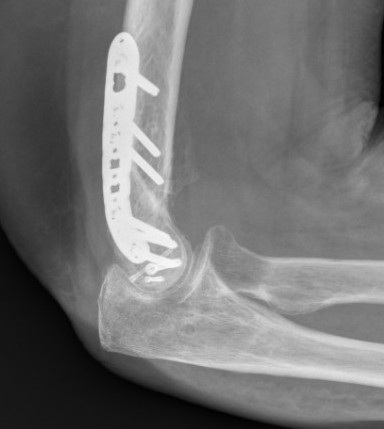

ORIF with PA screws and posterolateral plate

Large capitellum fracture / lateral column ORIF with plate and screws